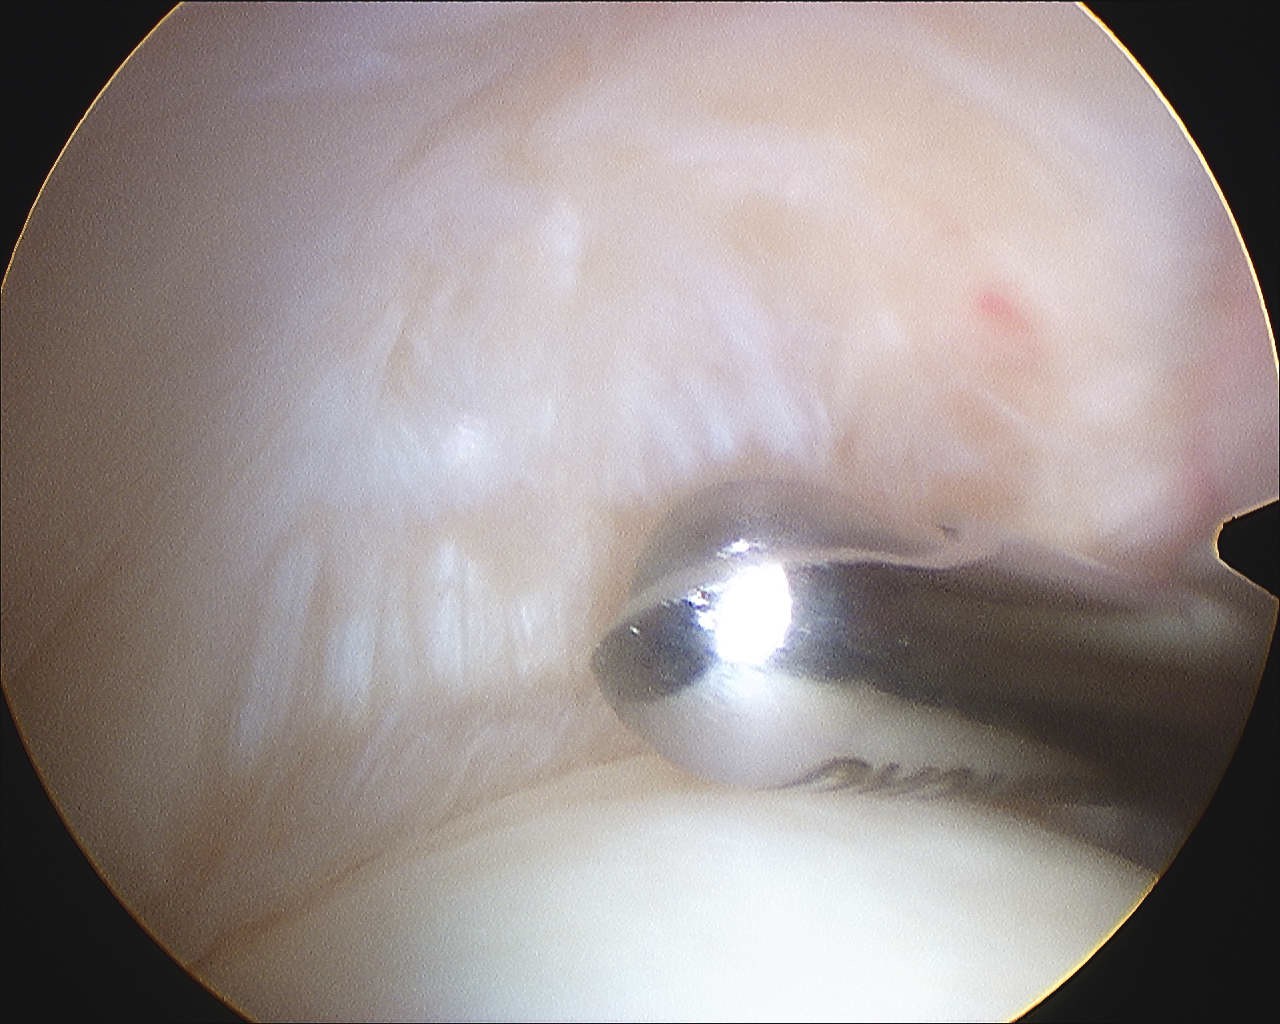

Articular side

Normal insertion of undersurface of the rotator cuff onto the footprint, with camera in glenohumeral joint